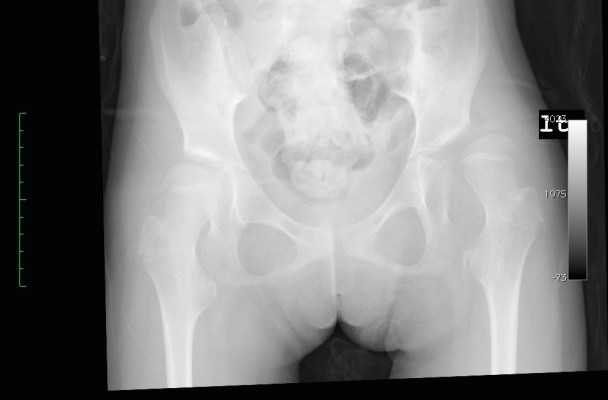

Standards of care, cerebral palsy and hips; what’s the deal?